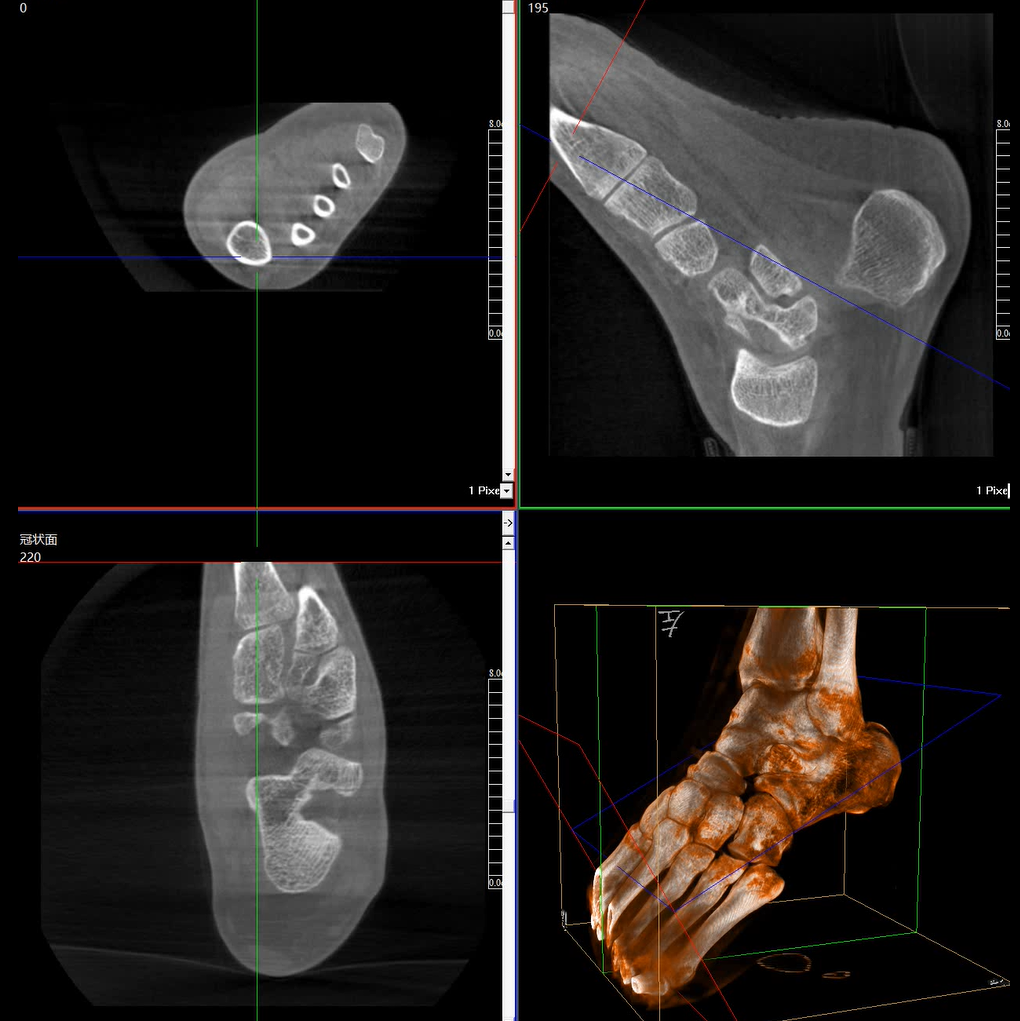

術(shù)中三維成像和橫斷面圖像提供多角度的手術(shù)診斷信息,輔助醫(yī)生進(jìn)行術(shù)中評(píng)估判斷,諸如骨折復(fù)位情況和內(nèi)植入螺釘?shù)某叽绾臀恢?,輔助手術(shù)更好地完成。